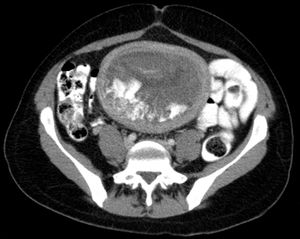

Hydatidiform mole on CT, sagittal view

Hydatidiform mole on CT, axial view

أما كيف يشخص الحمل العنقودي ، فعن طريق إجراء تحاليل لمعرفة نسبة هرمون الحمل التي غالباً ما تكون عالية جداً بالمقارنة مع الحمل الطبيعي• وهناك طريقة أخرى ، وهي إجراء الفحص بالأشعة الصوتية ، بحيث يكون مايشبه العاصفة الثلجية ، وهذا يدل على أن المشيمة غير طبيعية ، وإذا وجدت جنين فهذا قد يدل على أنه حمل عنقودي جزئي وعادة ما يكون الجنين غير طبيعي ويتوفى داخل الرحم في الأشهر الأولى من الحمل •